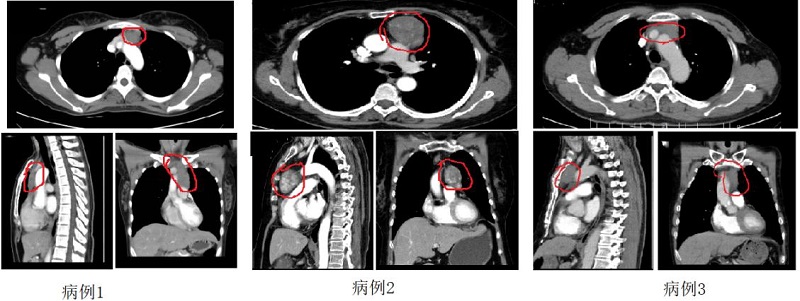

近期,陕西省核工业二一五医院胸外科团队再次完成多例剑突下胸腔镜胸腺瘤扩大切除术,手术效果,患者均顺利出院。 病例1 陈某因肌无力就诊神经外科,入院检查后发现纵隔肿瘤,肿瘤与无名静脉关系紧密,侧切口手术...